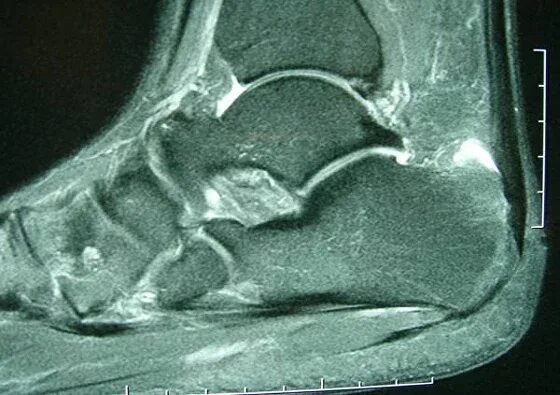

Ахиллобурсит мкб 10 у взрослых